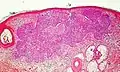

Nodular basal-cell carcinoma

.jpg.webp)

Nodular basal-cell carcinoma (also known as "classic basal-cell carcinoma") accounts for between 50% and 80% of all BCC.[2] It most commonly occurs on the sun-exposed areas of the head and neck.[2] Histopathology shows aggregates of basaloid cells with well-defined borders, showing a peripheral palisading of cells and one or more typical clefts.[17] Such clefts are caused by shrinkage of mucin during tissue fixation and staining.[18] Central necrosis with eosinophilic, granular features may be also present, as well as mucin. The heavy aggregates of mucin determine a cystic structure. Calcification may be also present, especially in long-standing lesions.[17] Mitotic activity is usually not so evident, but a high mitotic rate may be present in more aggressive lesions.[17] Adenoidal BCC can be classified as a variant of NBCC, characterized by basaloid cells with a reticulated configuration extending into the dermis.[17]

Cleft.